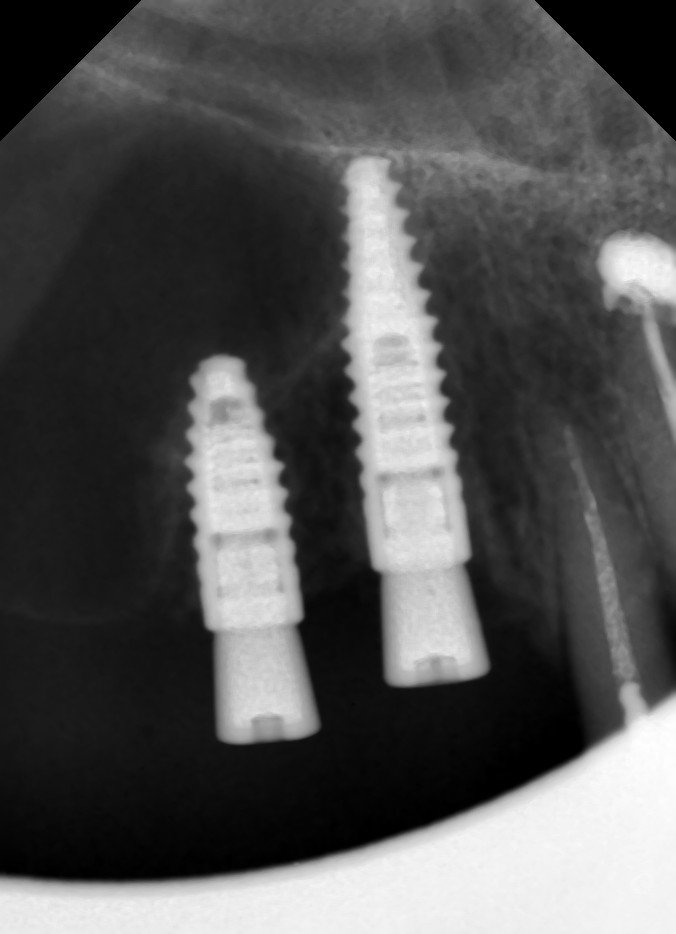

Tornillo roto en un implante de conexion interna cuyo cuello tiene un color verdoso, posible diametro 3,5??¿Qué marca de implante puede ser? Muchas gracias por vuestra colaboración